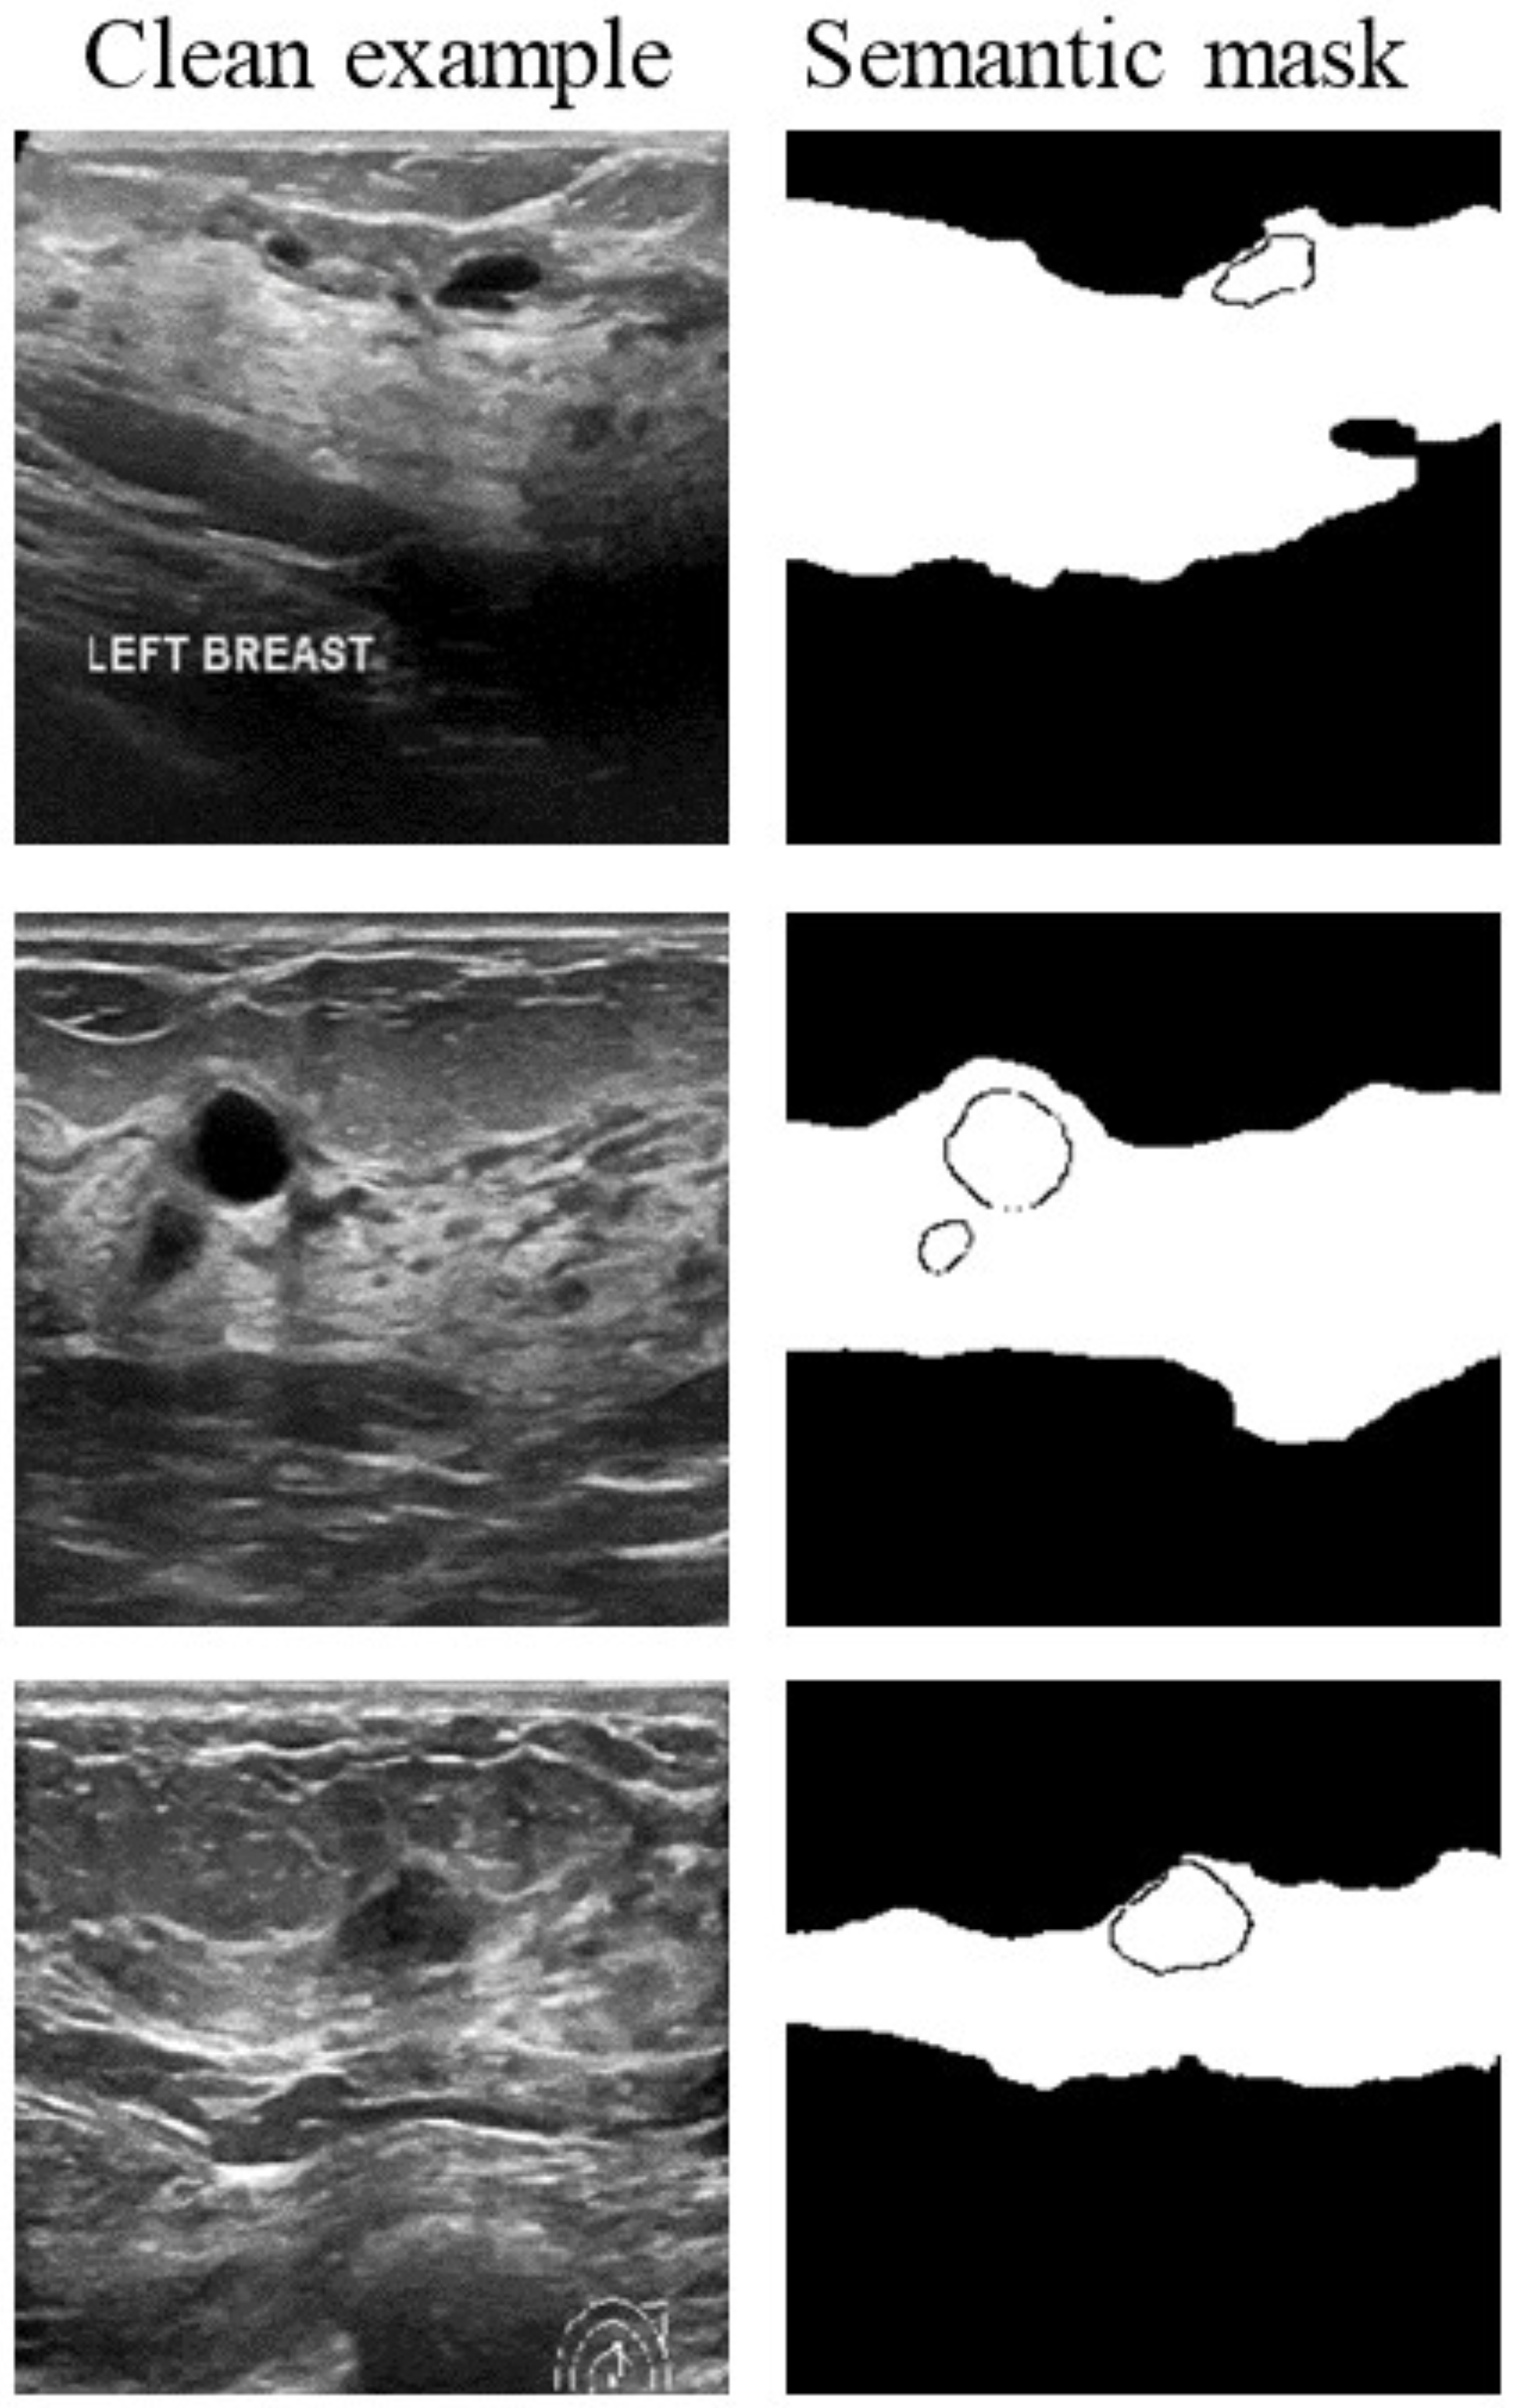

- The proposed semantic-aware search algorithm avoids invalid searches by cropping the search space using semantic masks from breast anatomy.

3.3. Semantic-Aware Search